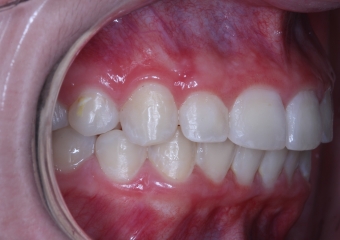

Lateral final - 2019